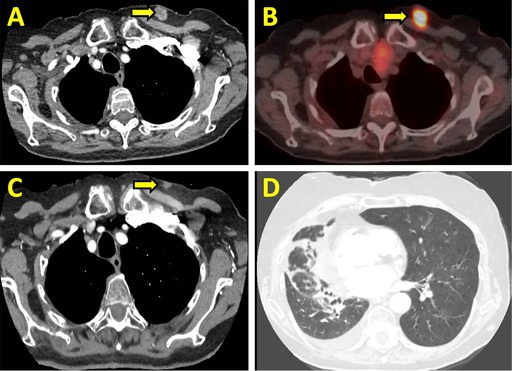

原发性肺平滑肌肉瘤是一种极为罕见的恶性肿瘤,占所有肺癌的不到0.5%。由于罕见,没有标准化的治疗指南。在被认为不能切除的病例中,预后尤其差。我们描述的情况下,一个90岁的妇女谁提出了进行性呼吸困难和咳嗽超过1个月。胸部计算机断层扫描显示一个大的右肺门肿块,延伸到右上叶和中叶,毗邻纵隔和心包膜。组织病理学分析证实为原发性肺平滑肌肉瘤。考虑到她的高龄和合并症,她不适合手术治疗。分子分析显示PDL1表达

Primary pulmonary leiomyosarcoma is an exceedingly rare malignancy, comprising less than 0.5% of all lung cancers. Due to its rarity, no standardised treatment guidelines exist. Prognosis is especially poor in cases which are deemed unresectable. We describe the case of a 90-year-old woman who presented with progressive dyspnea and cough over 1 month. Chest computed tomography revealed a large right hilar mass extending into the right upper and middle lobes, abutting the mediastinum and pericardium. Histopathological analysis confirmed primary pulmonary leiomyosarcoma. Given her advanced age and comorbidities, she was not a candidate for surgical intervention. Molecular profiling demonstrated PDL1 expression < 1% and no targetable mutations, ruling out the option of immunotherapy. She was managed with palliative radiotherapy followed by pazopanib therapy. Serial imaging demonstrated disease control, with an extended survival of approximately 5 years. Despite a median reported survival of 14 months, our patient achieved prolonged survival, highlighting the importance of an individualised therapeutic approach for elderly patients with rare malignancies.